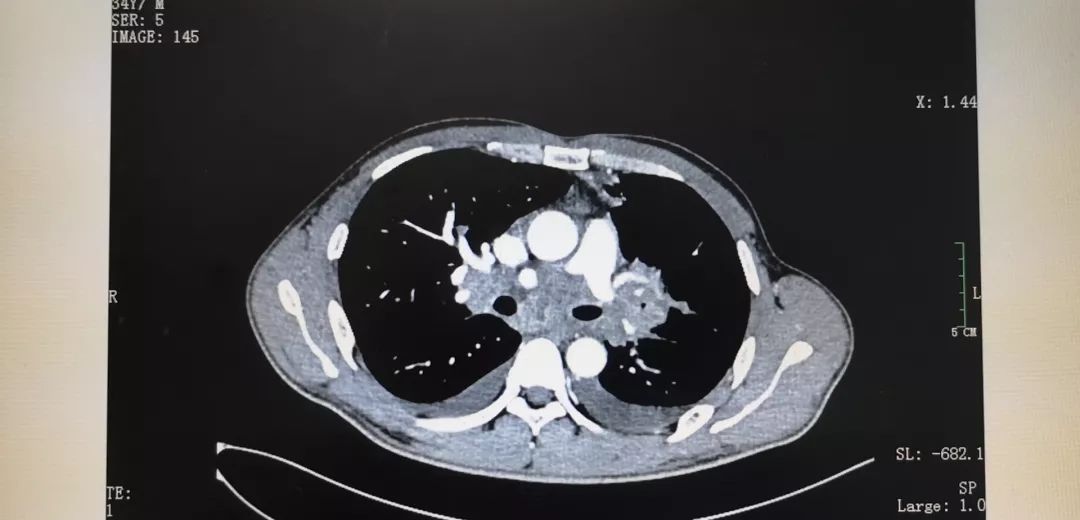

肺部恶性肿瘤ct图片